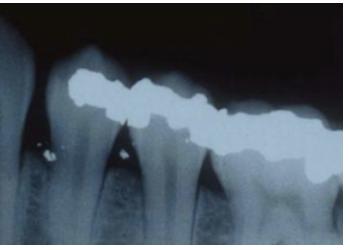

Amalgam Tattoo

A

Traumatic implantation of amalgam particles into mucosa

* See clinically & radiographically

Don’t need to biopsy to treat

How well did you know this?